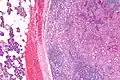

Micrograph of an acinic cell carcinoma (right of image) and acinar glands (parotid gland - left of image). H&E stain.

Histopathologic features

Basophilic, bland cells similar to acinar cells. Growth pattern: solid - acinar cells, microcytic - small cystic spaces mucinous or eosinophilic, papillary-cystic - large cystic lined by epithelium, follicular - similar to thyroid tissue.

These tumors, which resemble serous acinar cells, vary in their behavior from locally aggressive to blatantly malignant.